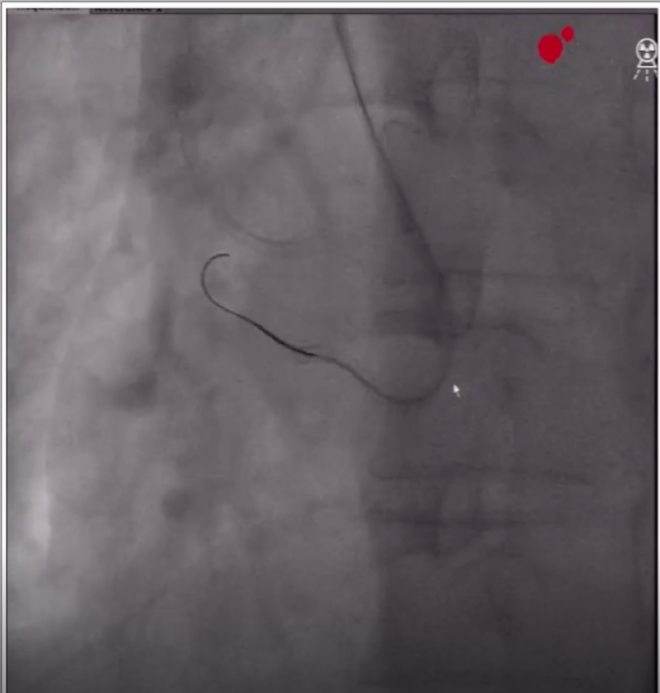

2、经7F桡动脉鞘送入7F AL0.75指引导管到达右冠开口,在corsair135cm微导管的支撑下送入runthrough导丝到达病变处。

runthrough导丝到达病变处

3、更换Pilot200导丝正向进入RCA中段内膜下,尝试调整导丝进入远端真腔不成功,为避免造成大的夹层和血肿,遂放弃正向开通,经右股动脉8F抗折鞘送入7F XB3.0指引导管至左冠,准备启动逆向方案。

正向Pilot200导丝位于RCA中段